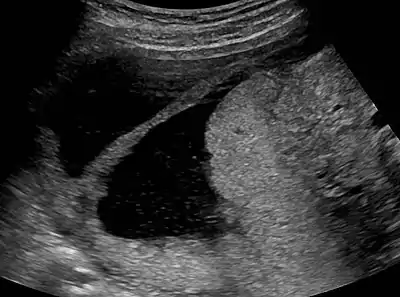

Ultrasound view.

The history of a pregnancy event followed by a D&C leading to secondary amenorrhea or hypomenorrhea is typical. Hysteroscopy is the gold standard for diagnosis.[13] Imaging by sonohysterography or hysterosalpingography will reveal the extent of the scar formation. Ultrasound is not a reliable method of diagnosing Asherman's Syndrome. Hormone studies show normal levels consistent with reproductive function.